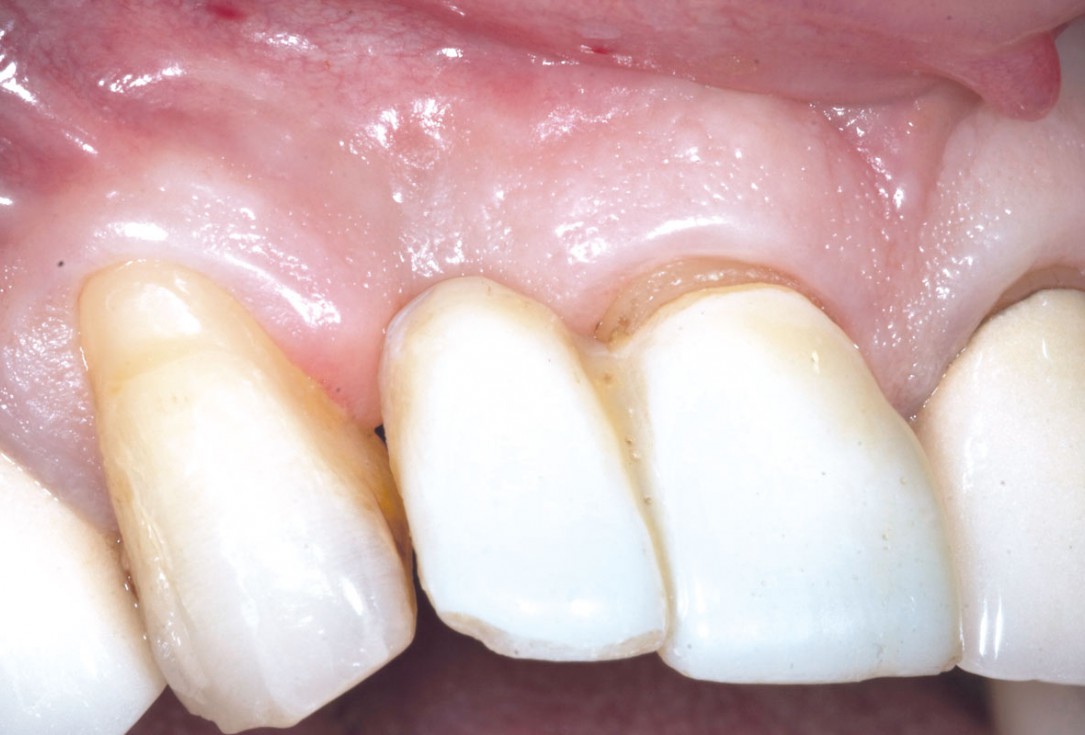

5/19 - 7 weeks after extraction of healing with a temporary tooth supported cantilever bridgeBone augementation with maxresorb® - Dr. R. Cutts